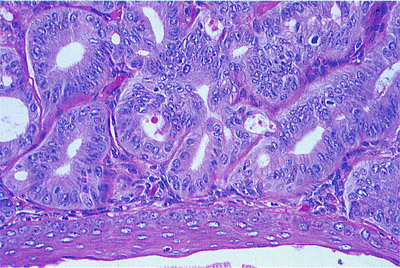

Κολποσκόπηση η οποία αναδεικνύει κυλινδρικό επιθήλιο όμοιο με του τραχήλου με εφαρμογή διαλύματος Lugol. Μπορεί να φαίνονται ως οζίδια ή κύστεις στο κολπικό σωλήνα. Παθολογοανατομικά διακρίνεται η πλακώδης μεταπλασία η εξελισσόμενη.